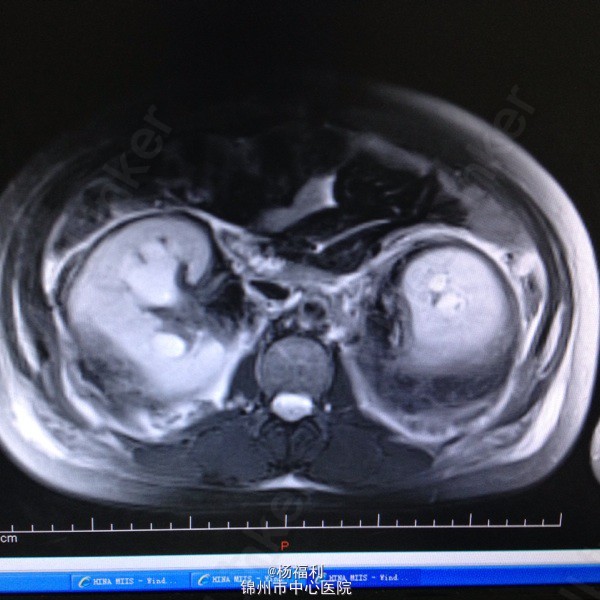

44岁女患。为消化科我会诊患者。 现病史:以上腹痛9小时为主诉入院。无发热及寒战、噁心未呕吐,无腹泻及黑便。 既往史:双眶炎性假瘤2年,口服激素治疗,并补钾。

查体:上腹部压痛,无反跳痛、右侧压痛明显,右肾区叩击痛,左肾区轻叩击痛,双输尿管走形区无压痛。 辅助检查;泌尿系彩超:双肾积水。 血白细胞:9.99*10^9。 肾功能正常。 全腹部ct及MRU检查:见图片。

诊断;真的不知道是啥病。 处理:暂时止痛处理。双肾病变。不知从哪里下手。

讨论:患者疾病和眶部肿瘤有关系吗? 和激素应用有关系吗? 最后建议患者去北京大医院进一步诊断治疗。 大神快快现身。